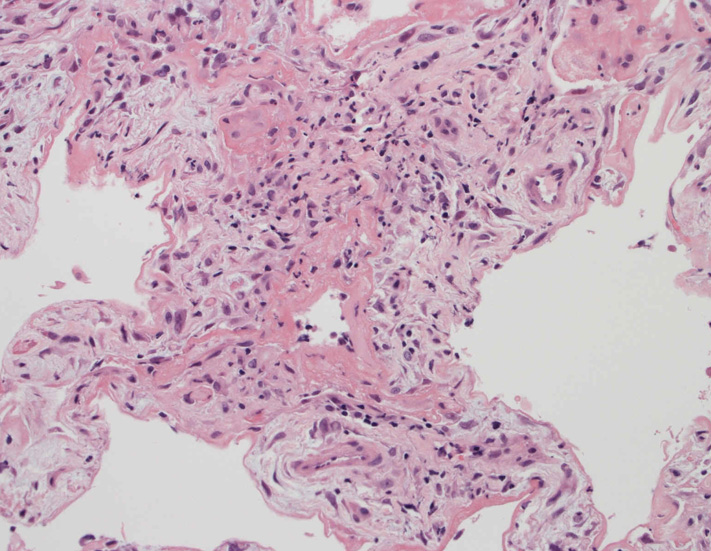

肺の病理所見

lung01.jpg

lung02.jpg

lung03.jpg

lung04.jpg

Fig.01Fig.02Fig.03Fig.04

肺毛細血管炎 capillaritis

肺胞壁に多数の好中球浸潤。肺胞腔内に出血。 capillaritisが起こるWegener' granulomatosis劇症型には, なかなか肉芽腫性病変を見つけることは難しい